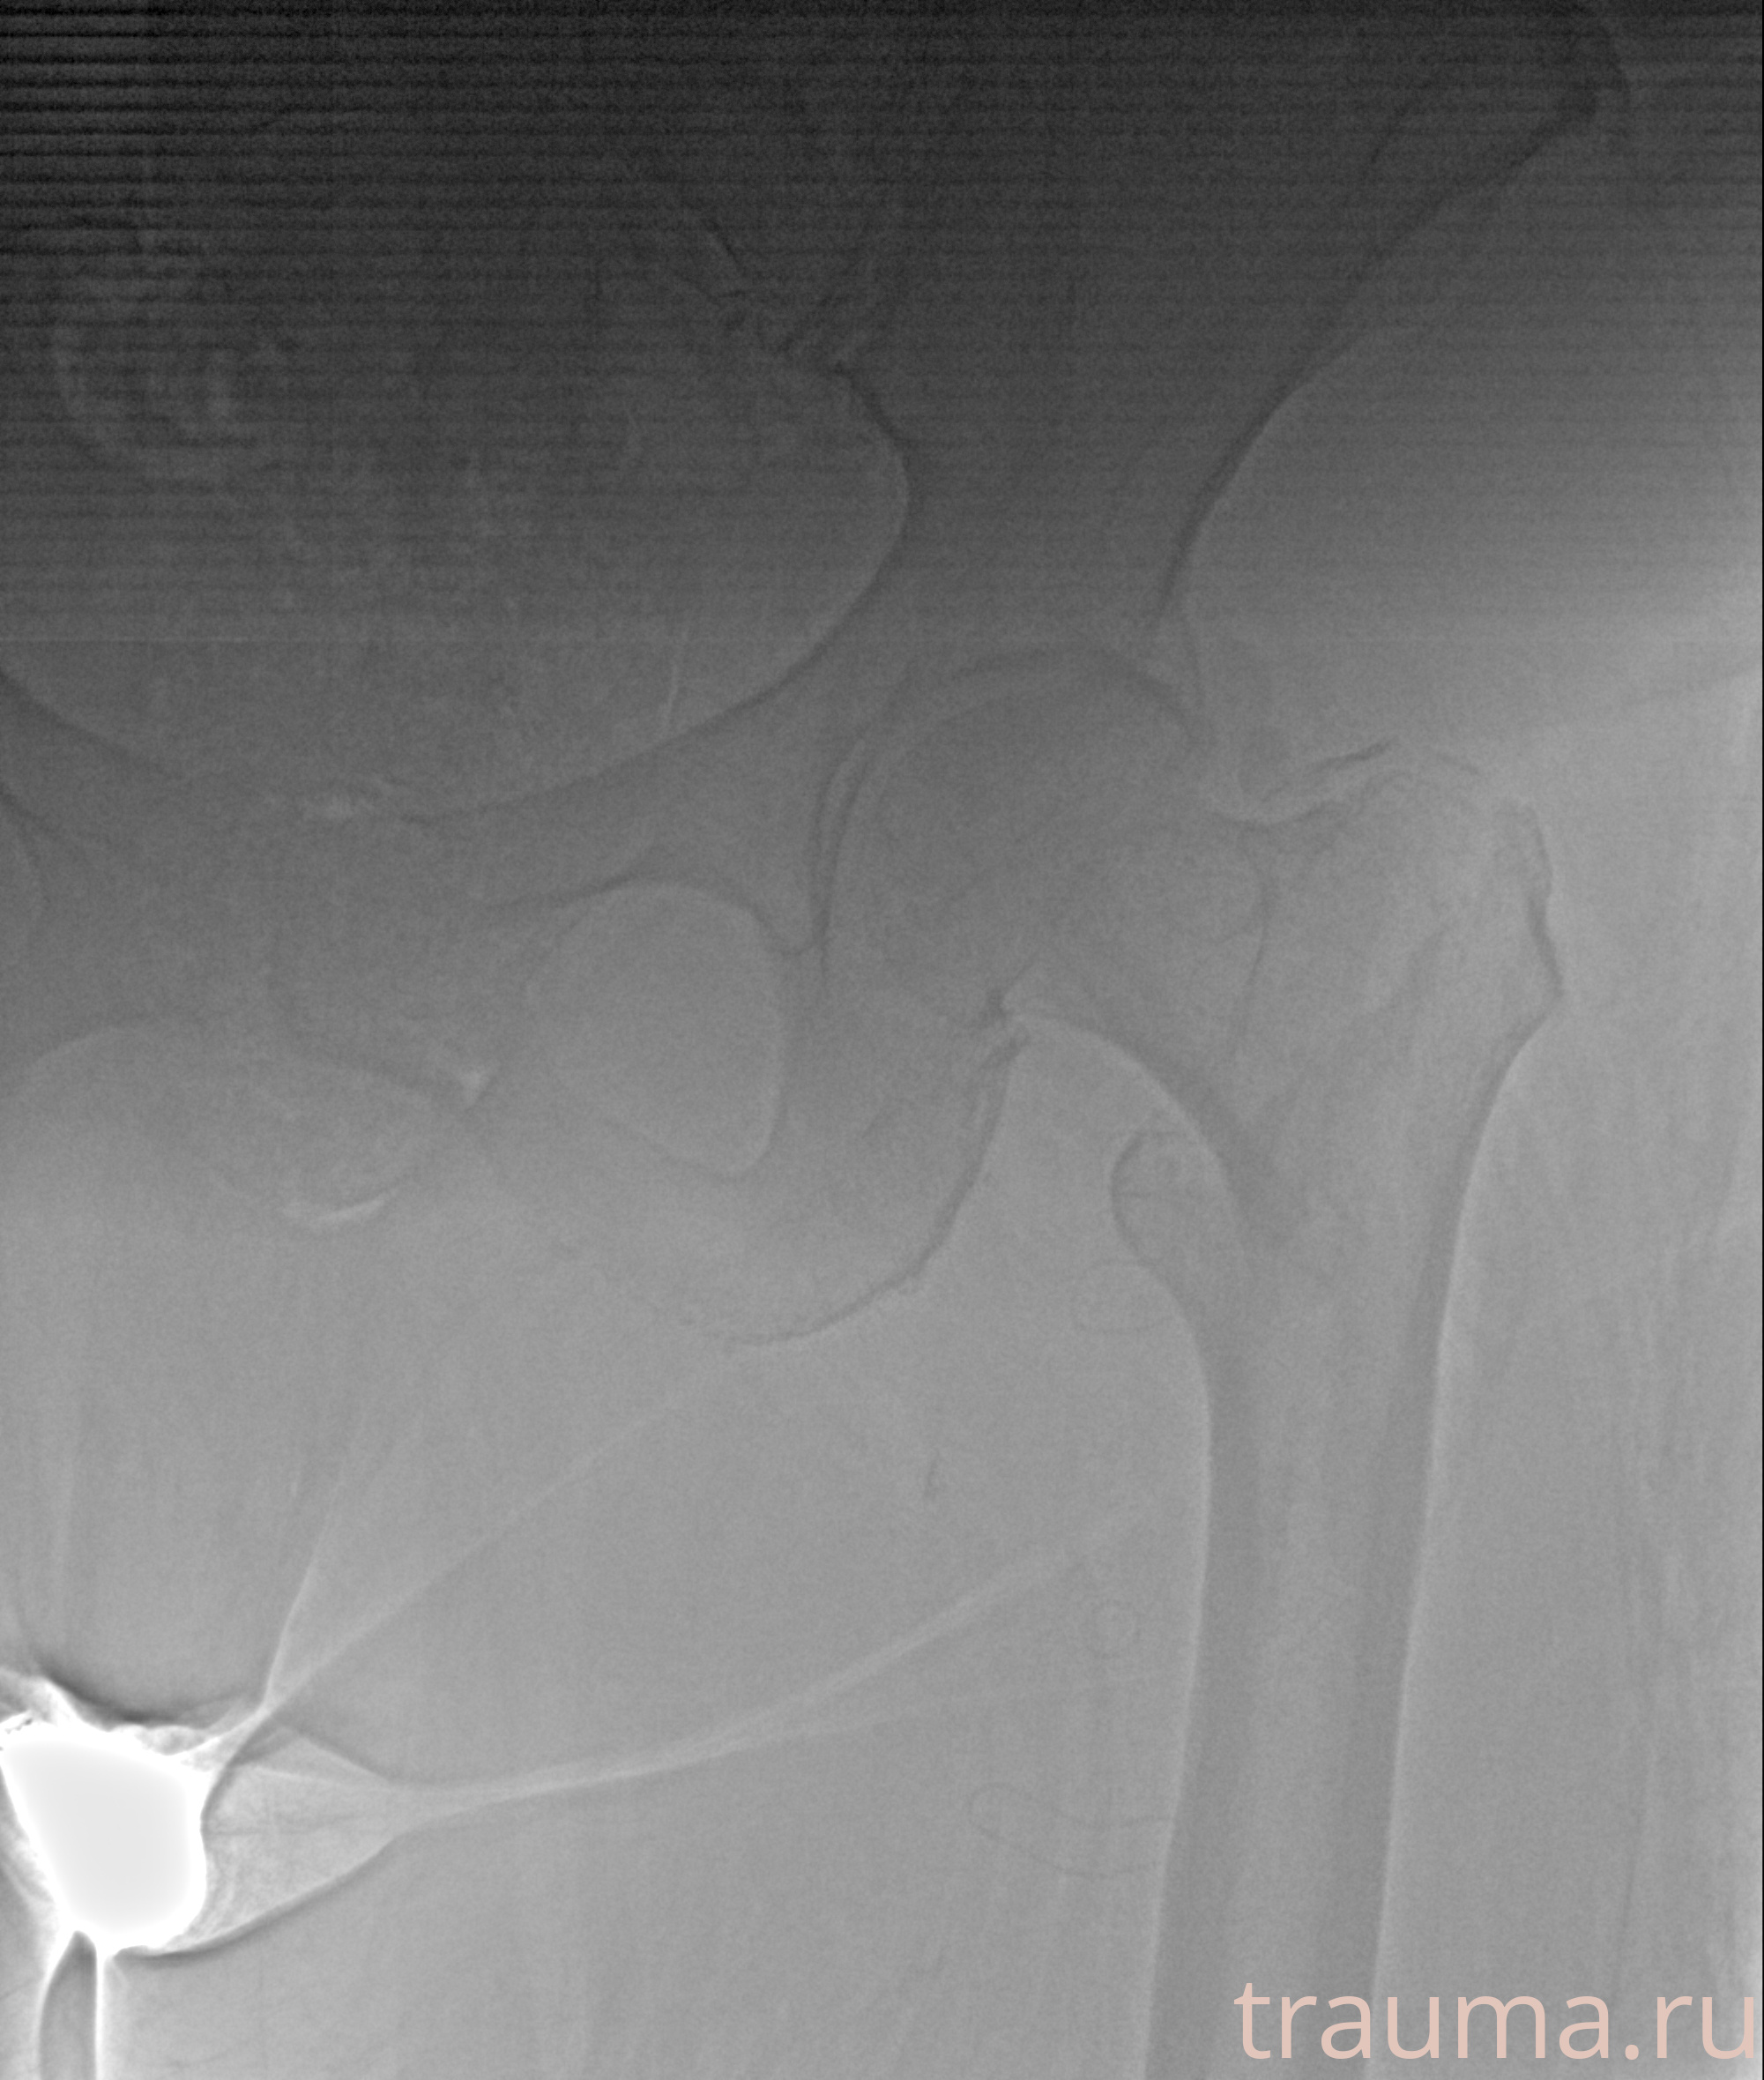

Рентгенограммы

Рентген на дому: по вашему адресу приезжает врач-рентгенолог, травматолог-ортопед с мобильным рентгеновским аппаратом, проводит диагностику травмы или заболевания, делает необходимые рентгенограммы, дает рекомендации по дальнейшему лечению. Получить качественные снимки в домашних условиях возможно благодаря уникальной методике, разработанной МосРентген Центром для института  Склифосовского